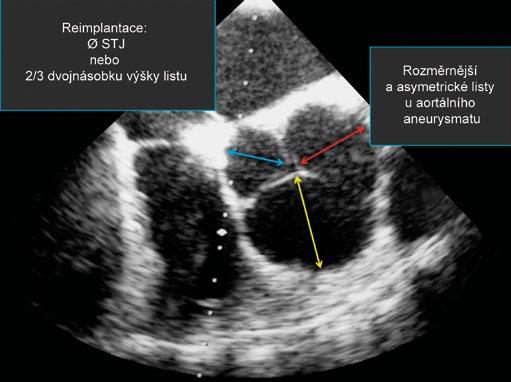

Různé diagnostické postupy a techniky si všímají bazálního prstence (BR), aortálních sinusů, sinotubulární junkce (STJ), vzestupné aorty a výtokového traktu levé komory (LVOT) (obr. 1-10). Jak již bylo uvedeno [4], bazální prstenec představuje myšlený kruh, který spojuje nejnižší body listů aortální chlopně [14]. V případě aortální nedomykavosti je bazální prstenec dislokován do výtokového traktu levé komory, naopak u aortální stenózy a retrakce listů se bazální prstenec posouvá do aorty. V některých případech je obtížné či téměř nemožné bazální prstenec definovat (obr. 1-11). Někteří autoři dávají přednost nejdistálnější části výtokového traktu levé komory na úrovni aortomitrálního ohybu. Ani tento bod není fixní – bod závěsu se posouvá směrem k volnému okraji předního listu mitrální chlopně v případě mitrální nedomykavosti [15] (obr. 1-12). Pravděpodobně nejspolehlivější a nejpřesnější je přímé měření Hegarovým dilatátorem v průběhu operace. U bikuspidální aortální chlopně je měření BR spojeno s dalšími specifickými obtížemi. Správné stanovení rozměrů BR je u záchovných výkonů na aortálním kořeni důležité vzhledem k tomu, že je zapotřebí stabilizovat nebo upravit správný poměr mezi BR a STJ [16]. Hodnocení aortálního kořene na úrovni sinusů rovněž vyžaduje obezřetnost. Obvyklé zobrazení představuje hruškovitě tvarovaný kořen se dvěma protilehlými sinusy. Tento průměr sinus-sinus ve skutečnosti nepředstavuje skutečný průřez středem aortálního kořene. Řez dělící kořen na dvě poloviny zobrazuje ve skutečnosti vzdálenost mezi sinusem a protilehlou komisurou (obr. 1-13). Navíc vzhledem k normální asymetrii aortálního kořene je nutno vzít v potaz řadu podobných dalších průměrů. Záchovné výkony na aortálním kořeni vyžadují přesnou kalibraci. Průměr STJ a výška listů aortální chlopně (2/3 výšky) spolu s výškou komisur představují základní chirurgické parametry. Chlopenní listy jsou zejména u aneurysmat aortálního kořene asymetrické a větší než normálně [17]. Měření všech rozměrů musí být doprovázena klinickým úsudkem.

Obr. 1-13 Průměr aortálního kořene. Řez dělící aortální kořen na ideální poloviny by vycházel od poloviny jednoho sinusu k protější komisuře. V důsledku této skutečnosti rovina klasického zobrazení aortálního kořene se dvěma (téměř) symetrickými sinusy neprochází skutečným středem kořene. Navíc vzhledem k přirozené asymetrii aortálního kořene i v důsledku onemocnění jsou tři vzdálenosti mezi odpovídajícím sinusem a komisurou různé. Koaptační zóna tří aortálních chlopenních listů neleží zpravidla ve středu kořene. Při dilataci nebo aneurysmatu aortálního kořene jsou chlopenní listy zpravidla rozměrnější a vykazují více asymetrie. Měření musí být proto hodnocena s klinickou rozvahou a chirurgickou zkušeností, protože je známo, že při reimplantaci aortální chlopně je jako referenční rozměr brán průměr STJ nebo 2/3 dvojnásobku výšky listu.